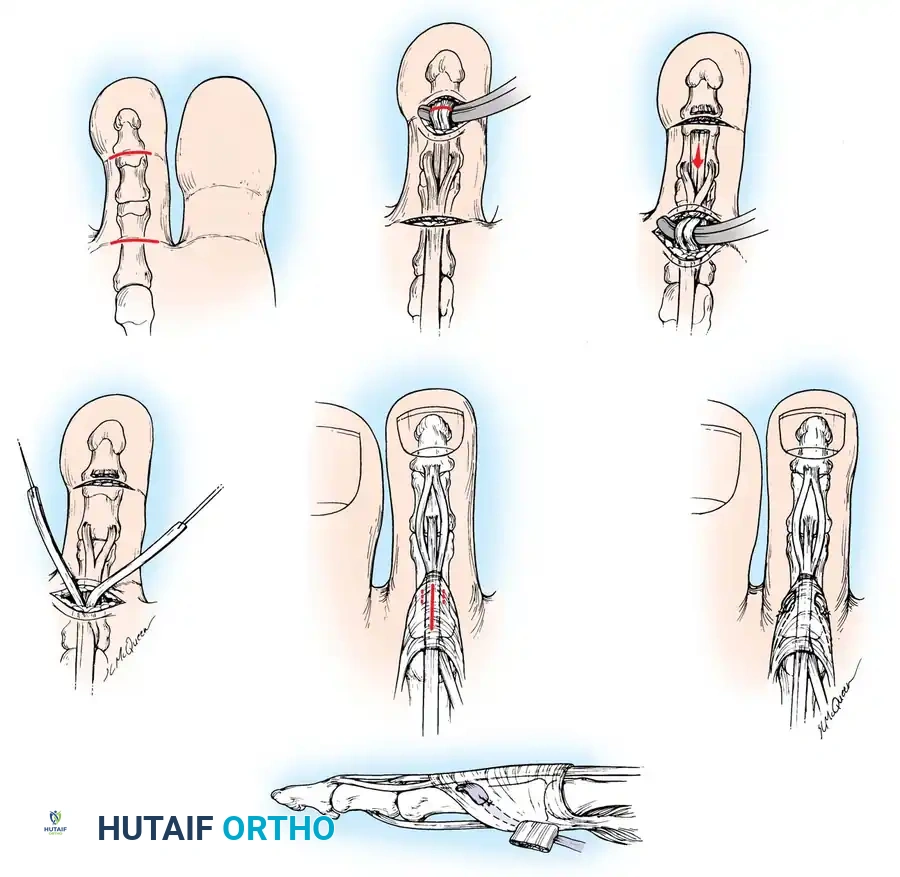

Operative Technique: Step-by-Step

1. Proximal Plantar Exposure

* On the affected toe, make a transverse plantar incision directly over the proximal flexion crease of the digit. Extreme care must be taken to preserve the neurovascular bundles located laterally and medially.

2. Tendon Identification and Release

* Open the proximal 3 to 4 mm of the fibrous pulley to expose the FDL tendon. This is best achieved by incising the pulley along its lateral border and reflecting it. Magnification loupes and a small round-end blade facilitate this delicate dissection.

* Topographically, this exposure is located at the middle third of the proximal phalanx.

* Identify the central tendon as the FDL. Confirm this by applying gentle, passive flexion and extension to the DIP joint while holding the proximal interphalangeal (PIP) joint in full extension.

* Elevate the FDL tendon. The vinculum longum will appear under tension; sever it using electrocautery to mobilize the tendon.

3. Distal Tenotomy

* Make a second transverse plantar incision at the level of the DIP joint.

* Perform a complete tenotomy of the FDL at its insertion, ensuring the plantar plate of the DIP joint is not violated.

4. Tendon Delivery and Splitting

* Return to the proximal incision. Hook the FDL tendon with a small hemostat (do not clamp the tendon substance) and deliver the distal segment into the proximal wound. Tenacious vincula may require gentle blunt force to release.

* Inspect the wound to ensure the two lateral slips of the flexor digitorum brevis (FDB) remain intact.

* Inspect the delivered FDL tendon to identify the shallow, linear furrow running longitudinally along its plantar surface.

* Using small forceps, hold one side of the free end while an assistant holds the other. Split the tendon longitudinally along this natural cleavage plane for 1.5 to 2.5 cm.

* Surgical Tip: Pull the tendon distally while plantarflexing the ankle. This provides optimal visualization of both sides of the tendon, preventing inadvertent complete sectioning of one half. Use the very tips of straight tenotomy scissors in the axilla of the split.

5. Dorsal Routing and Fixation

* Moisten the split tendon slips with sterile saline.

* Make a 1.5 to 2 cm longitudinal midline incision on the dorsum of the proximal phalanx. Carefully identify and retract or cauterize the dorsal digital veins.

* By sharp dissection, identify the trailing edge of each lateral band of the extensor mechanism while the skin is retracted, including the dorsal hood aponeurosis, to prepare for the routing of the split flexor tendon slips.

* Using a curved hemostat, create a tunnel passing from the dorsal incision, around the medial and lateral borders of the proximal phalanx, to the proximal plantar incision.

* Grasp the respective slips of the split FDL tendon and pull them dorsally. The slips should embrace the proximal phalanx like a sling.

6. Tensioning and Suturing

* With the ankle held in a neutral (90-degree) position, hold the MTP joint in approximately 10 to 15 degrees of plantar flexion.

* Overlap the two slips of the FDL tendon over the dorsal aspect of the proximal phalanx and the extensor mechanism.

* Suture the slips to each other and to the extensor aponeurosis using non-absorbable or slowly absorbable sutures (e.g., 3-0 or 4-0 braided polyester).

* Ensure the tension is sufficient to hold the MTP joint in slight plantarflexion without manual support.

* If concurrent bony procedures (such as a Weil osteotomy or PIP arthrodesis) are performed, a smooth 0.045-inch Kirschner wire may be driven retrogradely across the PIP and MTP joints to maintain alignment during the initial healing phase.